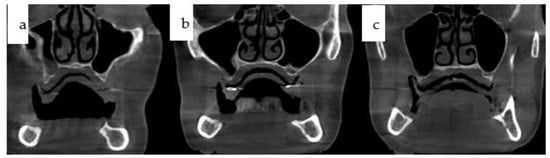

Figure 2. (ac): Three cone-beam coronal views from the same patient in Figure 1 depict the reduced horizontal and vertical bone stock in the edentulous maxilla, displaying typical sequelae of atrophy-related centripetal bone loss.